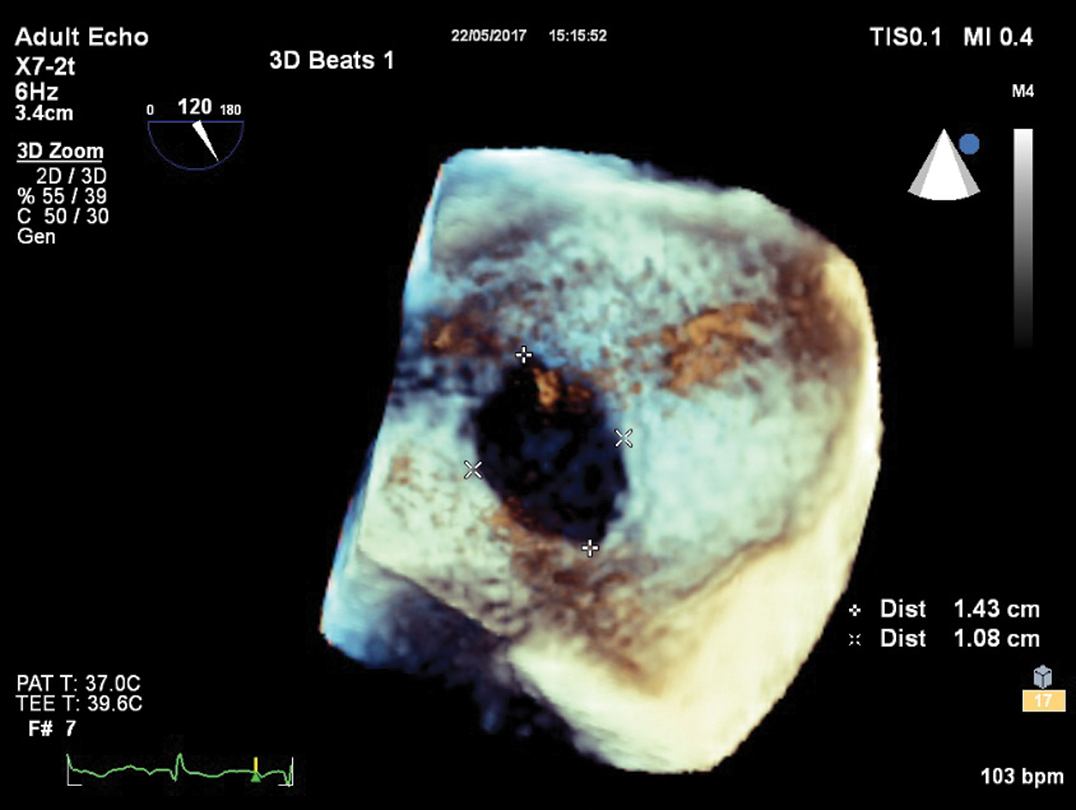

A 37-year old woman with a history of cervical rib surgical resection due to thoracic outlet syndrome (total occlusion of the left subclavian artery and significant stenosis of both left and right subclavian veins) presented with dyspnea on exertion (NYHA II functional class) and intermittent palpitations of 4-month duration. Ten years prior to presentation, the patient had spontaneous deep vein thrombosis extending from the veins of the left lower leg up to the left common femoral vein, the etiology of which was not elucidated despite extensive imaging and laboratory investigation including thrombophilia testing. For this reason, the patient was on oral anticoagulation therapy. At the time of admission, the ECG of the patient showed sinus rhythm with right bundle branch block. Transthoracic echocardiography (TTE) showed evidence of right ventricular volume overload (dilation of right heart chambers) with no signs of pulmonary arterial hypertension, presence of a large left to right shunt at the level of the interatrial septum and normal biventricular function. The pulmonary to systemic flow ratio (QP/QS) was 2.2. Transesophageal echocardiography (TEE) confirmed the presence of a moderate sized (14 × 11 mm) isolated ostium secundum ASD with adequate rims for percutaneous closure (Fig. 1).

Figure 1: Mid-esophageal view of atrial septum with three-dimensional transesophageal echocardiography showing a moderate sized ostium secundum defect (15 mm × 11 mm)